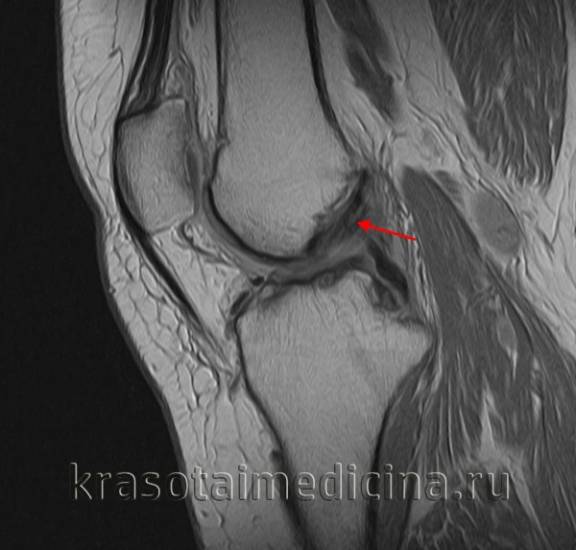

МРТ коленного сустава показывает повреждение (отек, разволокнение, частичный разрыв) передней крестообразной связки.

image